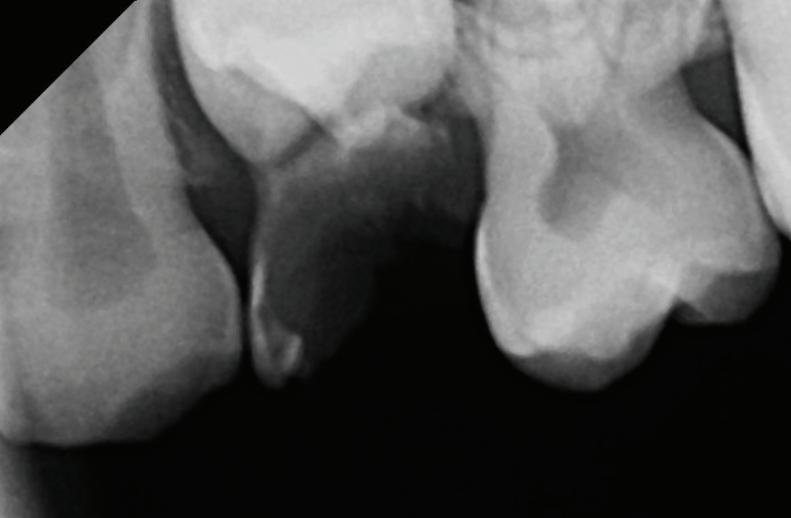

Thumb-sucking and pacifier use are natural self-soothing habits for infants and toddlers, but prolonged use can negatively impact dental development. If these habits continue beyond age 3, they may cause long-term changes in the shape of the mouth, alignment of the teeth and overall bite.

Common orthodontic issues include an open bite (where the front teeth don’t meet), a crossbite (where the upper jaw becomes too narrow), and protruding front teeth, which increase the risk of injury. These changes can also affect speech development, swallowing, breathing (snoring) and facial growth.

The ideal time to stop is between ages 2 and 4, before the adult teeth start coming in. If your child struggles to quit, gentle reminders, rewards and distractions can be effective. If the habit persists past age 5, or you notice changes in tooth positioning, an orthodontic evaluation is recommended.

Seeing an orthodontist by age 7 can help identify bite problems early and prevent more extensive treatment later. In some cases, simple interventions, such as a special appliance, can help break the habit and guide proper jaw development. Addressing these concerns early ensures a healthier, more confident smile for your child as they grow. Please call us for a free consultation if you have any concerns about your child’s bite.